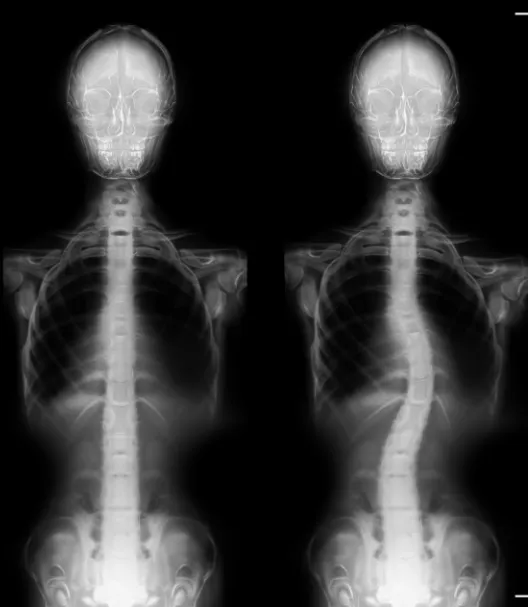

Are you in search of the finest chiropractor in CITY*, dedicated to caring for scoliosis? Typically, scoliosis begins as a subtle curvature in the spine that gradually intensifies over time. A scoliosis diagnosis occurs when the spine deviates more than ten degrees to either the right or left when facing a medical examiner. As scoliosis advances to more severe stages, it can bring about significant health consequences.

Scoliosis manifests as an abnormal bend or curve in the spine, deviating from the ideal vertical alignment of a healthy spine. The exact origin of this curve can often be elusive. In its early stages, it may begin as a minor bend due to a single vertebra's misalignment. Over time, the body compensates by developing musculature that continues to pull the spine into lateral curves to maintain a level head position.

Often, parents or close associates are the first to notice scoliosis, as the shoulders and pelvis no longer appear level. A thorough physical examination assesses gait and utilizes visual and manual evaluations to determine the extent of spinal curvature. An Adams Position Test, involving the patient bending forward as far as possible, can reveal the presence of an issue. If a noticeable curvature is detected, an X-ray will be employed to assess the severity of scoliosis.